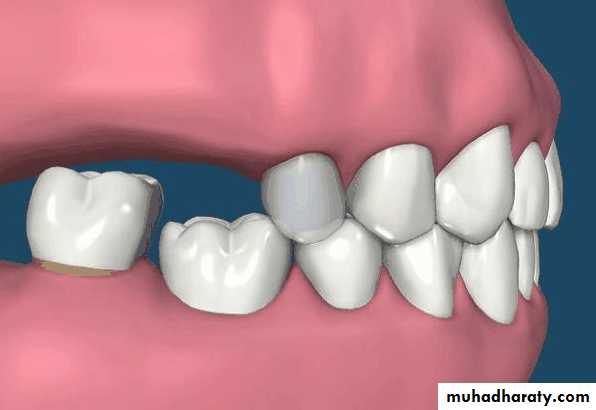

Interarch space

Lack of sufficient inter-arch distance- difficult for placing the teethFrequently it is caused by maxillary tuberosity that is too large in vertical height- surgical reduction vertical height is necessary for satisfactory replacement of the missing teeth.

• Treatment over erupted teeth

• If the tooth is extruded above the occlusal plane because of lack of an antagonist –• Treatment

• Moderately extrude tooth – aprox 2mm - enameloplasty.

• If the extrusion is greater than 2 mm or if the tooth does not lend itself to enameloplasty, the placement of a crown is indicated.

• Severely extruded teeth – contacting the opposing ridge & if alveolar bone followed eruption remove the tooth and recontour the bone is necessary

Occlusal plane

Occlusion plane may be irregular because of extrusionOne or more unopposed teeth.

Such conditions require corrective procedures if an acceptable occlusion is to be developed.